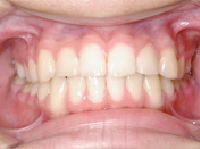

1) 主訴 前歯で咬むことができない

2) 診断名 前歯部開咬

3) 初診時年齢 25歳

8) 考えられる治療効果 咀嚼能力および能率の向上、構音機能の改善、口唇等の審美性の改善

前歯部開咬の患者さんでは、前歯をお互いに挺出させる(引っ張りだすこと)ことが多く、その

結果、前歯の歯根吸収や歯茎の退縮が生じやすくなります。これをさけるためにはゆっくりと歯

を移動させなければならず、治療期間が長くなったりします。